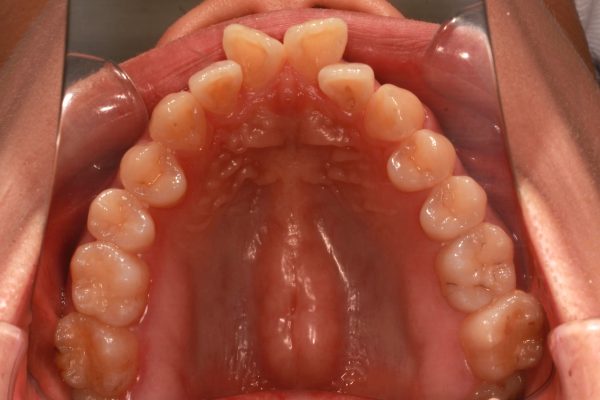

25歳 女性 「 八重歯 を治したい」 ( ハーフリンガル装置 )

25歳の 女性 です

「 八重歯 を治したい」との事で来院されました。

典型的な ”八重歯”です。

奥歯の噛み合わせは悪くありません。

犬歯を はじめとする前歯がガチャガチャの状態です。

正面から見ますと お顔に対して正中がズレています。

この ズレも治したいとのことです。

正中偏位 を伴う 叢生 です

上下左右の 抜歯を行い 前歯を後方に移動させました。

ハーフリンガル装置 (上だけ裏側)で治療を行いました

2017年の11月13日にスタートして

2019年の9月6日に 終 了しました。

治療期間は 22か月でした。

”八重歯” と 正中偏位の状態は改善されました

口もとの 印象が 大きく変わり自信をもって笑える との事でした。

25歳 女性 側方歯の開咬を伴う 叢生 治療期間23か月 上顎は舌側(リンガル)装置、下顎は唇側矯正装置(ホワイトワイヤー)を使用した第一小臼歯の抜歯治療 参考治療費 約92万円 (精密検査から終了まで) 矯正治療に伴う副作用の歯肉退縮、知覚過敏、失活、歯根吸収などは認められませんでした。